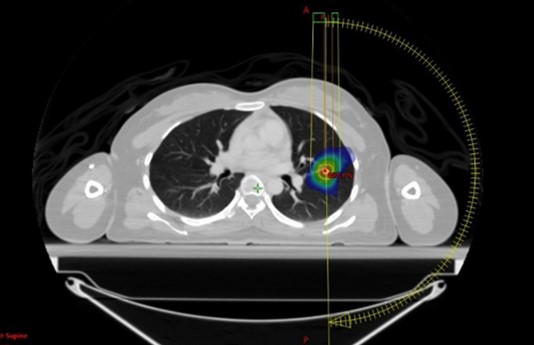

撮影した画像をもとに、放射線治療医・医学物理士・放射線技師が協力して治療計画を作成します。PET-CTやMRIなどの画像を撮影した場合には、それらの画像も活用しながら治療計画を行います。治療計画完成後は、複数の測定器を使って実際に計画通り正確に放射線が照射されているかを慎重に確認しています。

肺SBRT